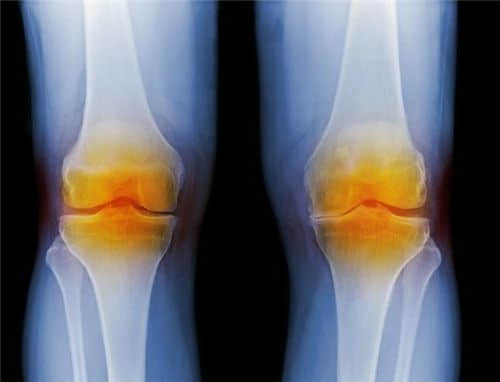

一、膝关节检测

50岁以上,膝关节内的软骨、半月板出现老化,关节周围的肌肉、韧带也因为萎缩,使得对膝关节的保护能力减弱。长期的负重,也使得关节面软骨产生磨损以及慢性炎症。

因此,不少人会感觉到明显的关节疼痛,若是半月板出现损伤而发生卡压时,除了疼痛更会导致行动不便,甚至无法下蹲。